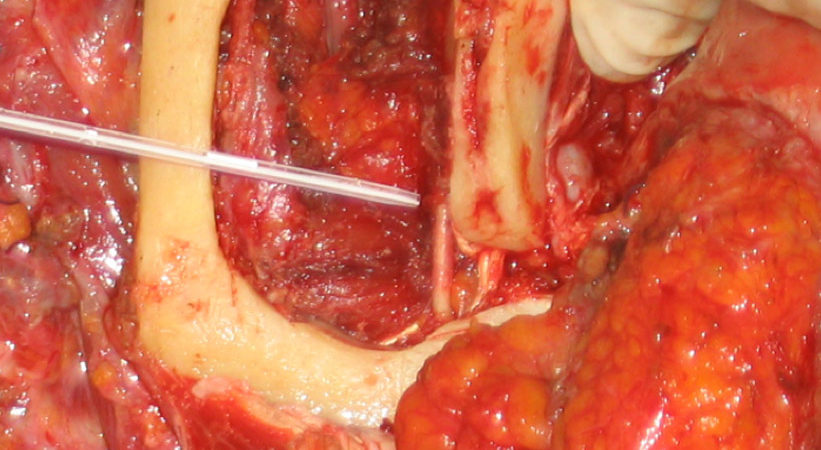

CASO CLINICO N° 2

Donna di 82 anni portatrice di un carcinoma squamoso multifocale del cavo orale infiltrante la mandibla T4N0.

Una mandibulectomia marginale è stata effettuata con tecnica piezoelettrica.